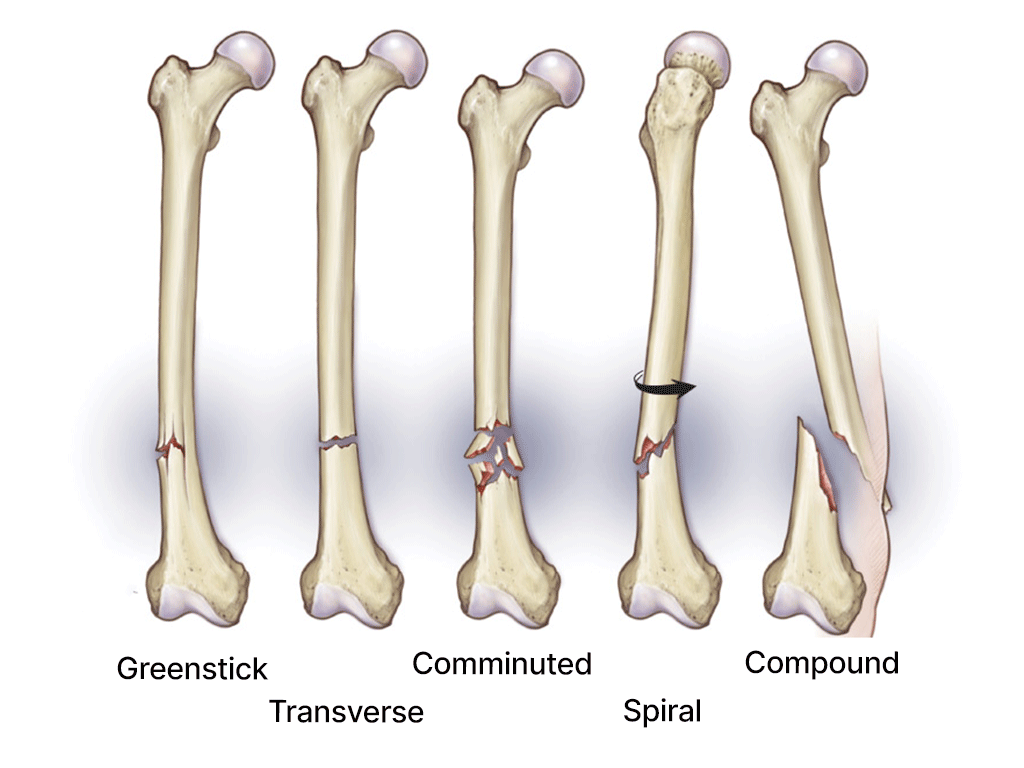

Broken bone

Acute sports injuries occur suddenly during activities. Examples include sprains, strains, fractures, and dislocations. Immediate steps can help manage the injury effectively:

Treatment varies based on the injury’s type and severity. Minor injuries often heal with home care, but serious injuries may require:

- Immobilisation with a cast or splint.

- Surgery for fractures or torn ligaments/tendons.